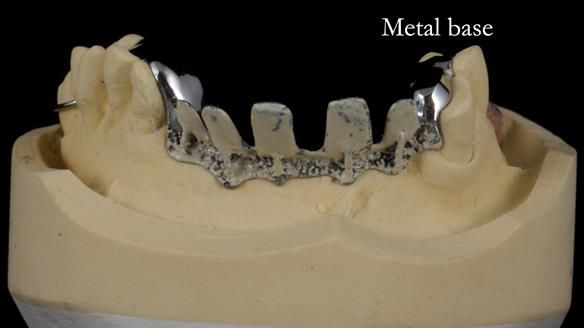

Keith’s case was one of the most challenging and rewarding cases I’ve treated this year. This 64 year old man presented with ill-fitting acrylic partial dentures that lacked stability, retention, and aesthetics. They constantly broke. He had lost the upper front teeth in a road traffic accident in his early 20s. The unopposed teeth had erupted, taking up space. After careful planning, we made a durable, metal-based upper partial denture/splint to address his dental concerns. He loved the outcome.

1. Denture design: A custom cobalt-chromium framework was Scandinavian-designed to maximise stability, protect the remaining teeth, and allow for future additions if needed.